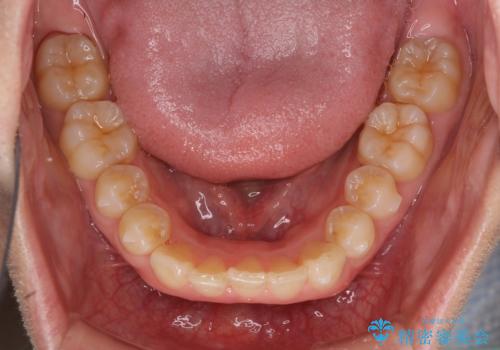

- 八重歯を気にして来院された患者様です。

八重歯の後ろの歯を1歯抜歯し、補助装置(リンガルアーチ)を用いて八重歯の位置を改善し、その後インビザラインにより矯正治療を行うこととしました。

下顎前歯が1本欠損したスリーインサイザーという状態であるため、上下の前歯の咬み込みが深くなったり、奥歯の咬み合わせが理想的なものとならなかったりという仕上がりになってしまいます。

前歯の見た目や奥歯の咬み合わせに、患者様が違和感を感じない状態として治療を終えました。